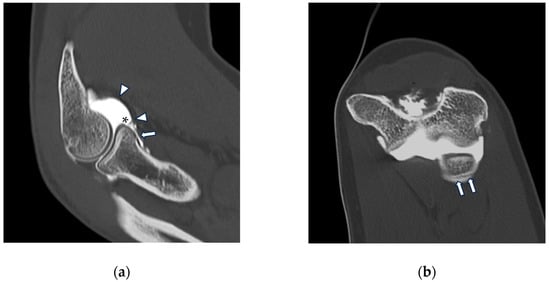

Figure 8.

CT arthrography of a patient with lateral epicondylitis subjected to multiple corticosteroid injections. (a,b) Coronal and axial images show extravasation of intra-articular contrast into lateral periarticular soft tissues through a large full-thickness tear of both the radial collateral ligament and the proximal common extensor tendon (white arrowheads). Diffuse thinning of radial head dish cartilage is also displayed (white arrows); (c) sagittal image also shows distal displacement of the annular ligament (yellow arrowhead) and cartilage fraying of the radial head side (yellow arrow).